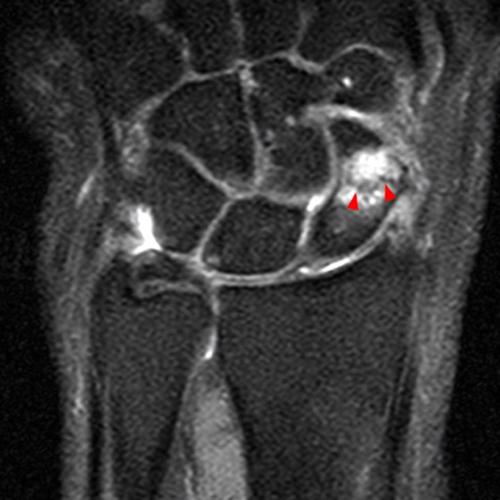

Figure 9: A 33-year-old female with radial-sided wrist pain for the evaluation of de Quervain’s tenosynovitis. Axial fat-suppressed proton density-weighted axial images at the proximal (9A) and mid-portion (9B) of the first extensor compartment demonstrate tenosynovitis with peritendinous fluid signal (arrows), overlying extensor retinacular and soft tissue edema, and marrow edema in the subjacent radius (arrowheads).